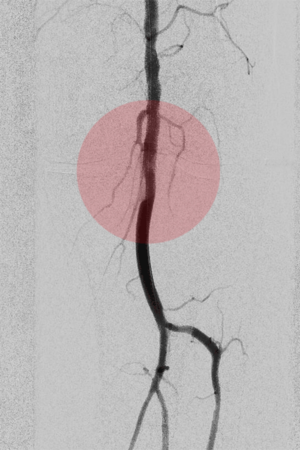

4. Atherektomie – mechanische Entfernung der Gefäßablagerungen

In speziellen Fällen der Durchblutungsstörungen ist es notwendig, die verschließenden oder einengenden Ablagerungen zu entfernen, bevor man das Gefäß erweitern kann. Dazu werden mechanische Katheter eingesetzt, die fräsen oder hobeln und das arteriosklerotische Material nach außen transportieren.